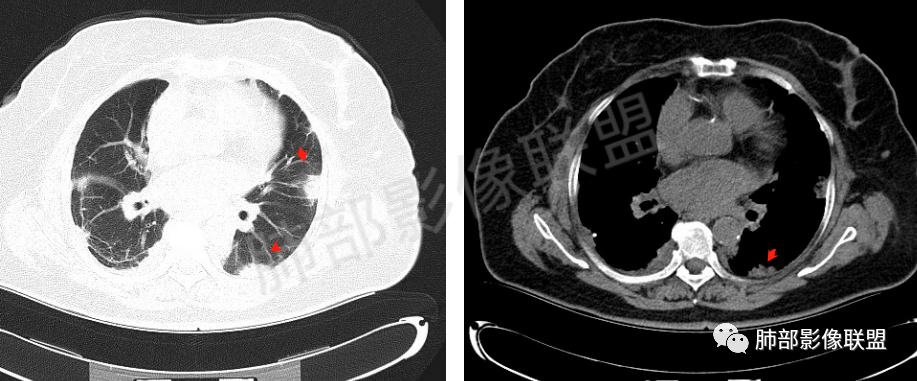

2、影像特点:双肺胸膜下为主、多发斑片影、结节样实变影及磨玻璃样密度影,大部分病灶边缘平直、边界清,磨玻璃密度病灶内可见细网格影,部分病灶内可见支气管扩张表现,部分支气管直达远端,部分中断于病灶中部。部分病灶有侧向融合趋势。

3、病例小结:老年女性,咳嗽咳痰伴气急逐渐加重,入院后有低热。部分炎性指标升高,肺部片影,可以符合感染性病变,但是血培养、支气管灌洗液培养等检查无阳性表现。但仍影警惕隐球菌感染,患者临床表现相对轻微,胸膜下病灶,磨玻璃影等。

影像上双肺多发磨玻璃影及实行密度影,对称分布趋势,op样改变,结缔组织相关性疾病需要排除。临床上可进一步查皮肌炎相关指标、仔细进行体格检查看看患者皮肤等情况。